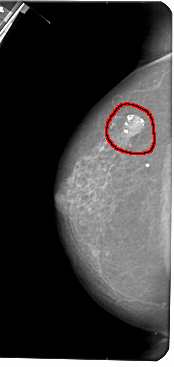

FILE: A_1306_1.LEFT_CC.OVERLAY

TOTAL_ABNORMALITIES 1

ABNORMALITY 1

LESION_TYPE CALCIFICATION TYPE AMORPHOUS DISTRIBUTION N/A

LESION_TYPE MASS SHAPE OVAL MARGINS CIRCUMSCRIBED

ASSESSMENT 2

SUBTLETY 5

PATHOLOGY BENIGN

TOTAL_OUTLINES 1

BOUNDARY